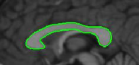

Figure 10: Segmentation of lungs using the mean template: (a) Initialization of template, (b) converged result. For the result shown in (c) and (d), an initialization similar to that shown in (a) was provided.

Yu et al. [35] reported good results for lung field and clavicle segmentation based on local differences of averages along the contour boundary. They start with an elliptical initialization and use dynamic programming to refine the contour. We also exploit the contrast between lungs and the rest of the body that X-ray imaging of the chest offers. We created a mean shape template from a set of training images using the methodology proposed in [36] and performed segmentation (refer Figure 10). The slight mismatch in shape between the mean template and the left lung in each image is evident from the results.